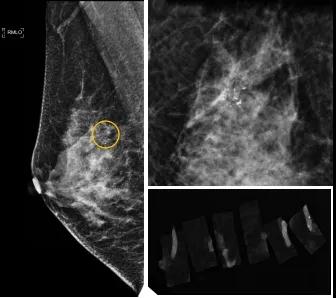

小到1—2mm的鈣化也能活檢!西安國際醫(yī)學中心醫(yī)院采用精準技術讓乳腺早癌無處可逃

46歲的某女士在西安國際醫(yī)學中心醫(yī)院體檢時,行乳腺X線攝影(俗稱鉬靶)發(fā)現(xiàn)右乳可疑簇狀鈣化,分布范圍不到1厘米,臨床觸不到,超聲很難發(fā)現(xiàn),但是這種鈣化風險比較高,依據(jù)國際BI-RADS指南需要明確病理!

西安國際醫(yī)學中心醫(yī)院影像診療中心陳寶瑩副主任帶領的團隊,采用全數(shù)字化乳腺X線三維立體定位系統(tǒng)可實施。這個團隊的成員大部分來自知名三甲醫(yī)院,有著十余年影像引導下乳腺介入診療的經(jīng)驗,X線引導穿刺定位和活檢例數(shù)居西北前列。為減少患者創(chuàng)傷,在詳細判讀了患者資料,并與患者及甲乳外科劉曉敏主任充分溝通的基礎上,團隊確定采用全數(shù)字化乳腺X線三維立體定位系統(tǒng)下實施粗針活檢。

當天,乳腺X線三維立體定位系統(tǒng)清晰顯示出了所有鈣化。為了獲取充足的組織量,保證病理診斷的準確性,團隊選用14G穿刺針并多點、多角度取材,組織取出后,又立即在高清標本攝影系統(tǒng)中進行投照,從而確定了取出組織中具有足夠的可疑鈣化。整個過程患者無任何不適,活檢結束后即回家觀察。

后期病理回報活檢組織條中均查見導管原位癌。該女士及家屬對西安國際醫(yī)學中心醫(yī)院早期發(fā)現(xiàn)并精準確診病變的技術給予了高度的贊揚。

乳腺導管原位癌屬于早期的腫瘤性導管內病變,有發(fā)展為浸潤性癌的傾向,需要早發(fā)現(xiàn)早治療,其預后明顯優(yōu)于浸潤性癌。2020年癌癥雜志的文章指出,近90%的導管原位癌僅表現(xiàn)為不可觸及的可疑鈣化,乳腺X線檢查是發(fā)現(xiàn)微小鈣化最敏感的方式,因此70–90%的導管原位癌是通過乳腺X線篩查發(fā)現(xiàn)。多年來國內外指南,如美國國家綜合癌癥網(wǎng)絡(NCCN)指南及中國抗癌協(xié)會乳腺癌診治指南均建議40歲以上女性每年通過雙乳X線檢查(鉬靶)進行乳腺癌篩查,高危人群建議提前進行篩查(小于40歲)。由于雙乳X線篩查的推廣,歐美等國家導管原位癌的檢出率極大提高,明顯降低了乳腺癌的死亡率。在我國規(guī)范進行乳腺X線篩查的人群比例比較低,很多人發(fā)現(xiàn)腫瘤時已經(jīng)為浸潤性癌,因此提醒大家高度重視規(guī)范的雙乳X線篩查。通過乳腺X線篩查發(fā)現(xiàn)的可疑鈣化需要在X線引導下精準定位,進行粗針穿刺或真空輔助旋切活檢,以獲得準確的病理學結果,給予及時有效的治療。